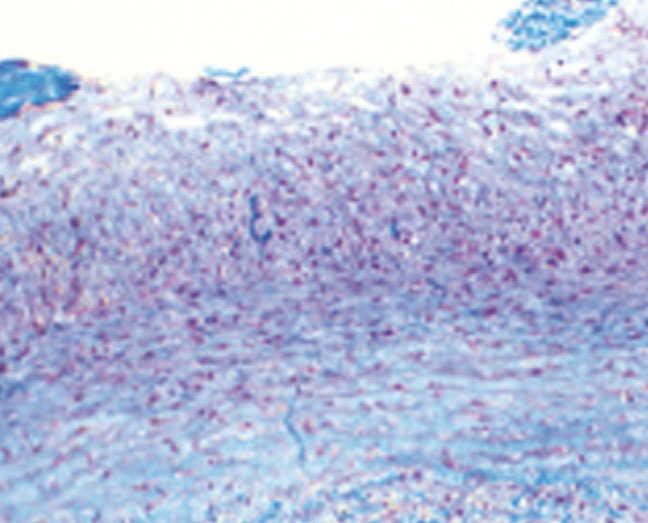

Patient who was hospitalised when she was two years due to HTA associated with loss of strength and sensation in her lower limbs. The arteriography showed decrease in aortic diameter, 20% stenosis at the right renal ostium, critical stenosis of the left renal artery and no flow in the left lower renal pole. The decision was made to perform left renal autotransplantation with renal anastomosis of the iliac artery and biopsy of the renal artery, which reported findings consistent with FD (Figure 1). She was discharged with minoxidil and propranolol.

Figure 1. Renal artery biopsy